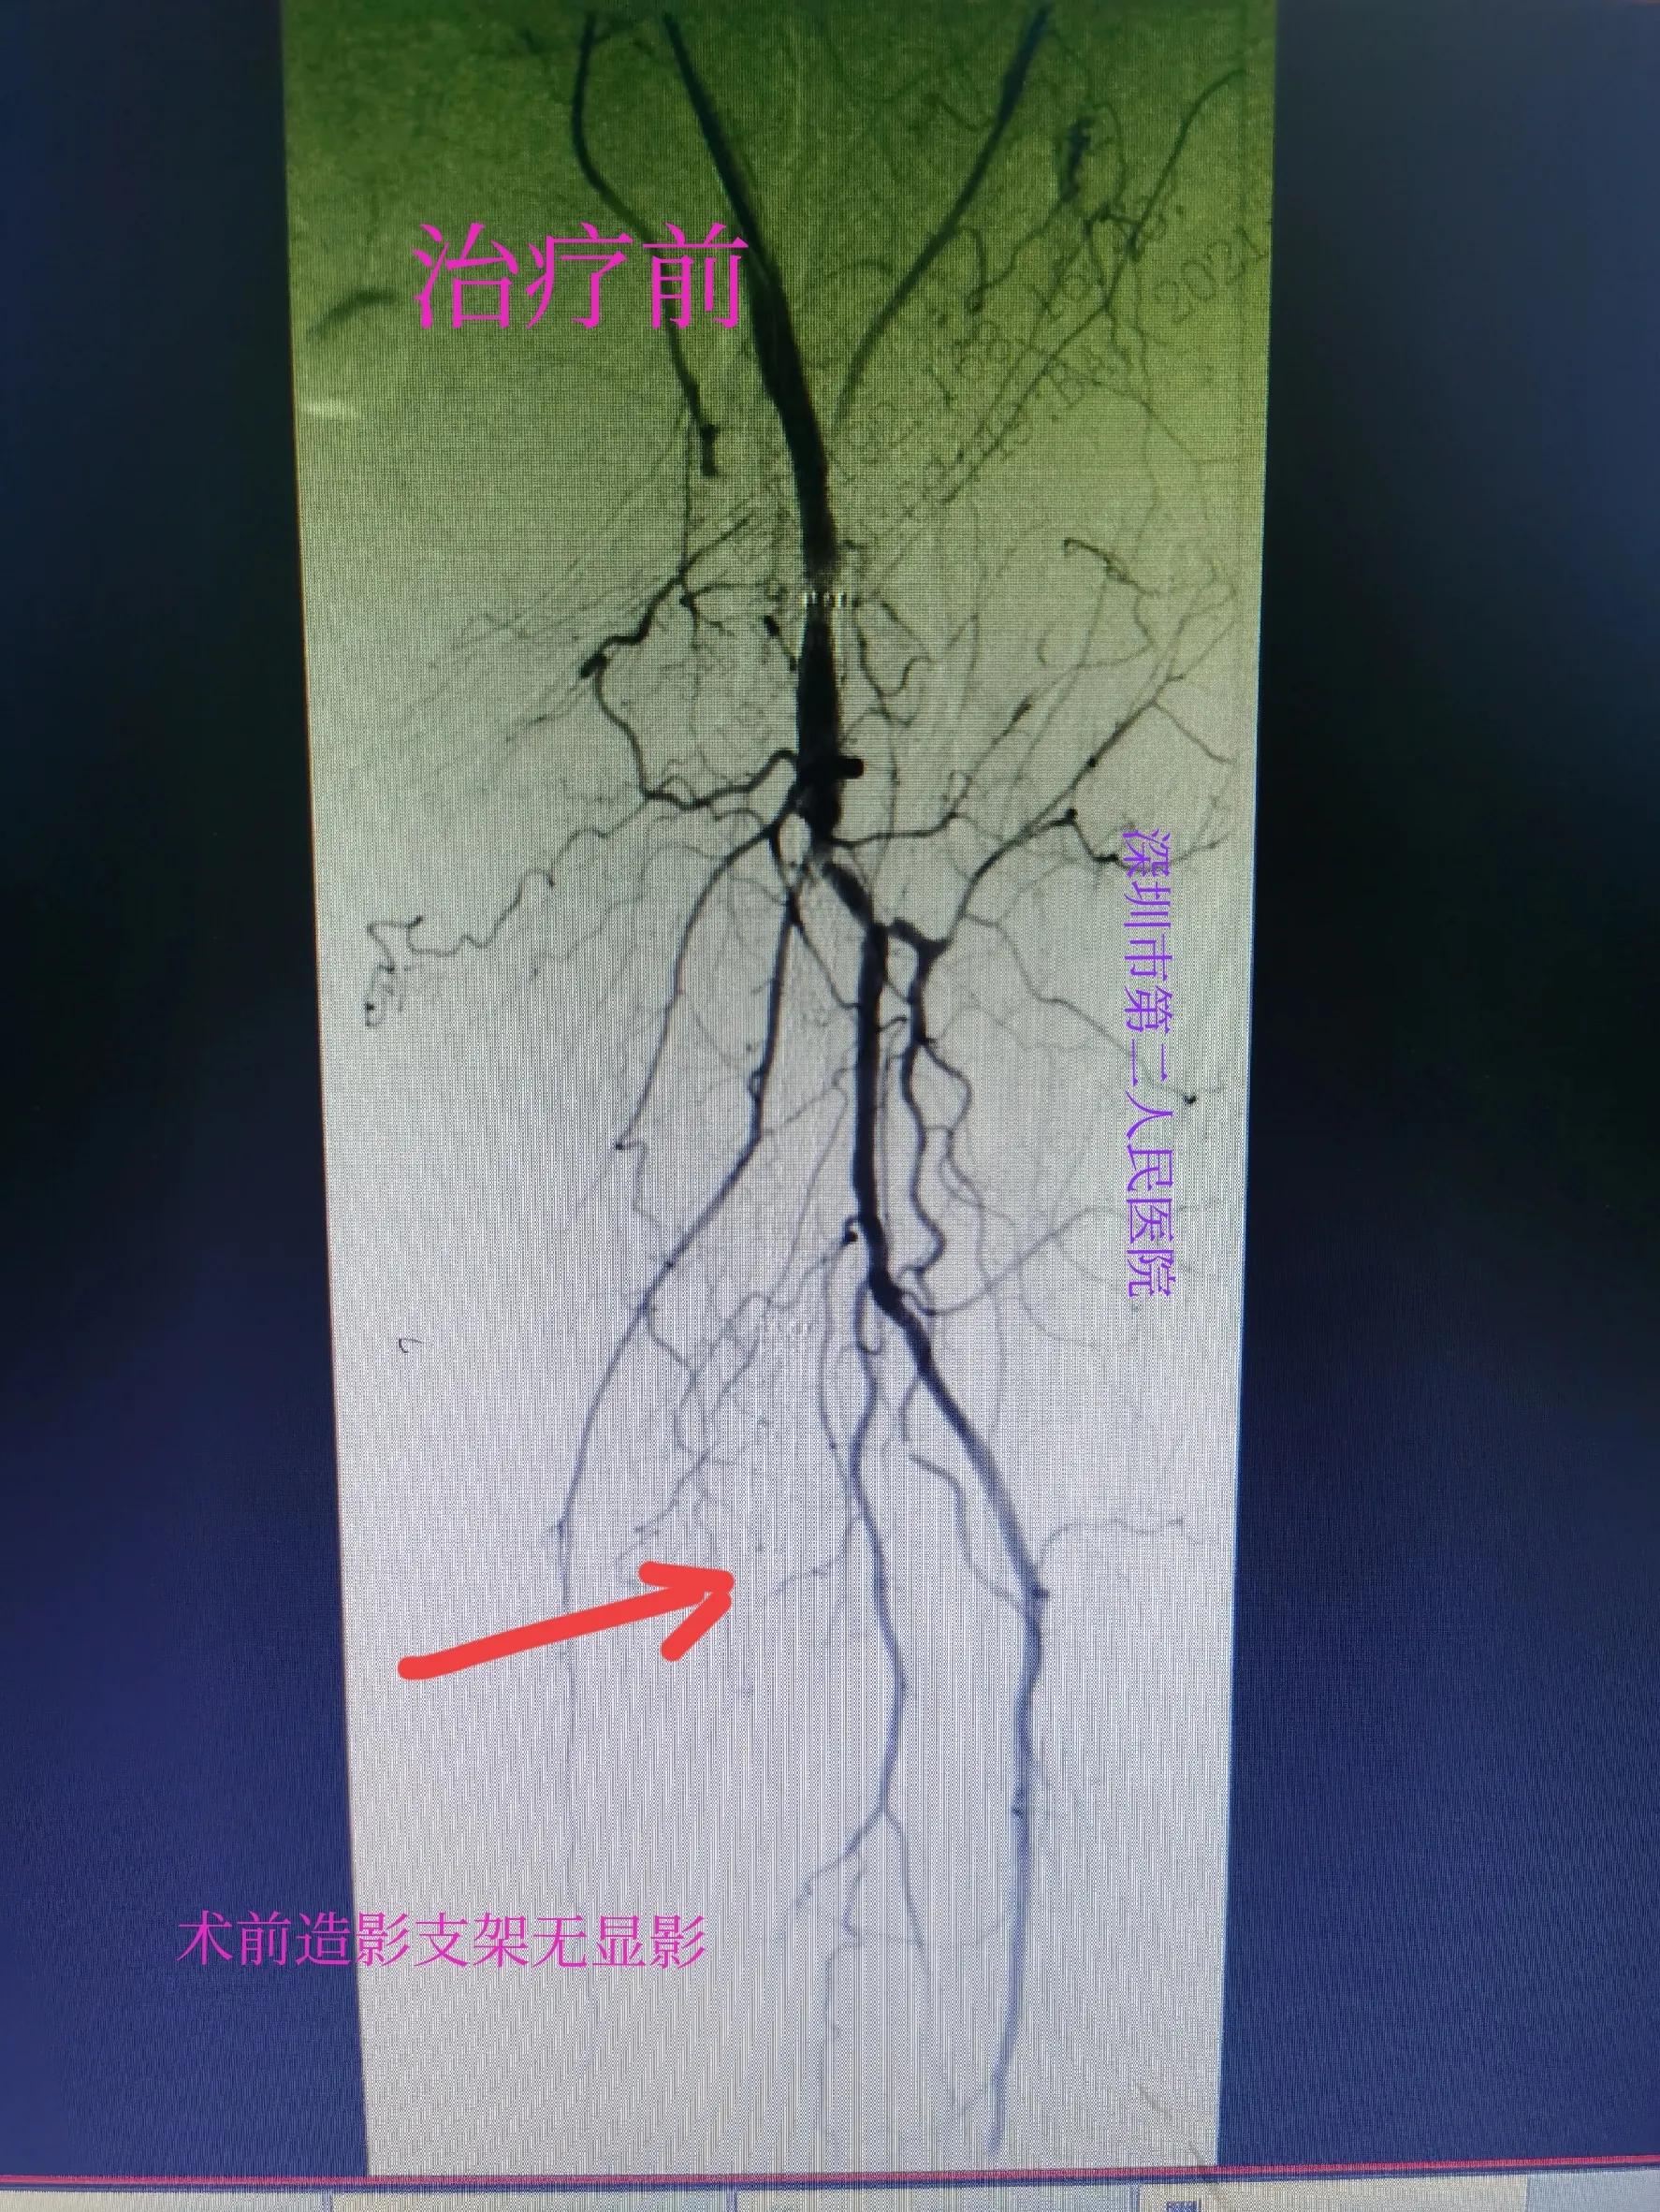

经过三个多小时的积极药物溶血栓、球囊扩张等治疗后,病人左小腿血流恢复,左足背动脉搏动良好。病人疼痛缓解,足部皮温恢复正常,比右腿还好。以下附上术前术后检查对比图。

支架堵塞

支架远端供血中断